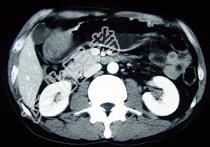

- 单项选择题女性,42岁, 腹痛、黑便1周,CT扫描见胃窦部圆形块影, 最佳的诊断是  (    )